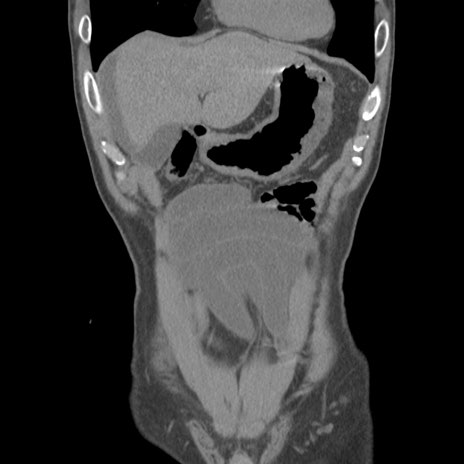

症例56 CT(冠状断像)

横断像